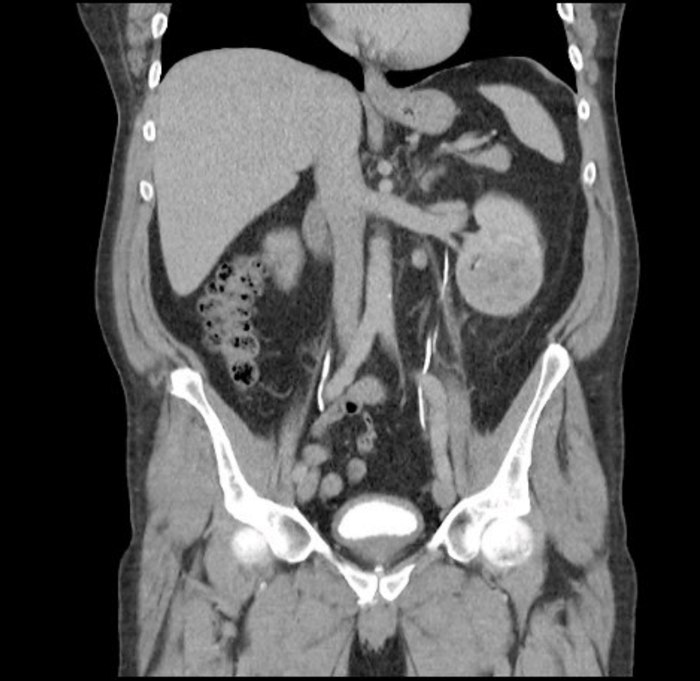

The investigations performed for sRCC should be the same as for any other RCC including blood tests to assess full blood count and renal function, imaging and histological diagnosis when appropriate. Imaging methods include ultrasonography (USS), computed tomography (CT) and magnetic resonance imaging (MRI). In CT imaging the renal mass is characterised by the features before and after administration of intravenous contrast. Enhancement of the mass measured in Hounsfield units of 15 or more is considered to have a high likelihood of malignancy [7]. CT and MRI give information about tumour extension, venous involvement, lymphadenopathy, involvement of the adrenals / surrounding structures and the state of the contralateral kidney. These imaging studies however cannot distinguish between the different histological subtypes or high-risk features [Figure 3].

Figure 3: CT scan showing a left RCC in coronal section but there are no

specific radiological features to differentiate conventional RCC from sRCC.